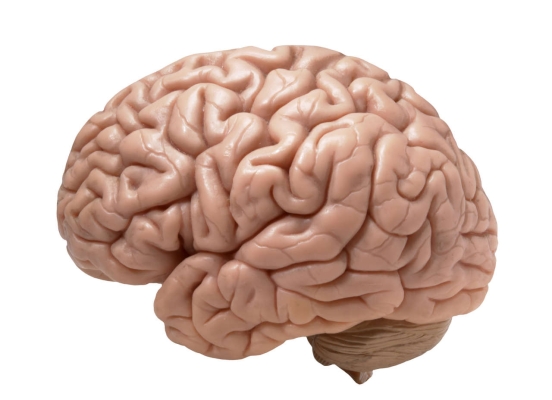

Il est désormais possible de mainténir le cerveau

Des scientifiques ont réussi à maintenir en vie pendant plusieurs heures les cerveaux de deux porcs après les avoir déconnectés de leurs corps. Un exploit aux accents de film d’horreur qui pourrait s’avérer crucial pour la recherche médicale.

« Être à côté de ses pompes » pourrait bien ne pas rester qu’une expression… Des scientifiques ont réussi l’exploit de maintenir en vie les cerveaux de deux porcs séparés de leurs corps ! Pour réussir cet exploit, les scientifiques ont sectionné les artères majeures reliant le cerveau au corps du cochon, puis ont « branché » l’organe à un contrôle circulatoire pulsatile extracorporel (EPCC). Cette machine « repose sur un algorithme qui maintient la pression artérielle, le débit et la pulsatilité à des valeurs proches des valeurs initiales » mesurées avant la séparation du corps, peut-on lire dans le résumé de l’article, publié le 25 août dernier dans Scientific Reports.

Le cerveau pilote de nombreux processus corporels (rythme cardiaque, respiration, cycles de sommeil et d’éveil, etc). Mais la relation est à double sens : il est, lui aussi, affecté par des mécanismes tels que la glycémie, la pression artérielle et l’oxygénation. Or, jusqu’à présent, impossible de dissocier les deux ! « Cette nouvelle méthode permet de mener des recherches sur le cerveau indépendamment du corps. Grâce à elle, nous pourrons répondre à des questions physiologiques d’une manière inédite ! », s’enthousiasme Juan Pascual, professeur de neurologie, de pédiatrie et de physiologie à l’UT Southwestern Medical Center et auteur principal de l’article dans un communiqué publié ce mois-ci.

Elle pourrait aussi permettre de « débrancher » le cerveau lors de certaines opérations chirurgicales, et ainsi éviter certains effets secondaires cognitifs parfois provoqués par les machines de dérivation cardio-pulmonaire. À cet effet, le dispositif a donc été breveté mais ne devrait pas être essayé sur l’être humain avant que toutes les réponses aux questions éthiques qu’il soulève n’aient été trouvées.